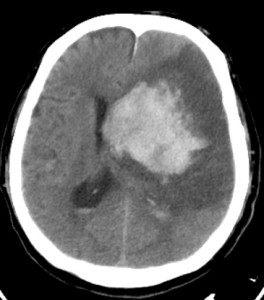

The study is a pooled analysis from the Oxford Vascular Study (OXVASC) and the Lothian Audit of the Treatment of Cerebral Haemorrhage (LATCH). It analyzed 674 first-time ICH patients over 1553 person-years. The cohort’s mean age was 74.7, 47% were male, and 51% were on antithrombotics before their ICH. Additionally, 22% had atrial fibrillation, and 47% had lobar ICH while the rest had non-lobar ICH.

The recurrent ICH rate was 3.2 per 100 person-years based on 46 events in the cohort. The ischemic stroke rate was 1.7 per 100 person-years from 25 events, and the rate for any serious vascular event was 7.9 per 100 person-years from 118 events. Lobar ICH had a higher risk of recurrent hemorrhage with a hazard ratio (HR) of 3.2 (95% CI 1.6-6.3; p=0.0010). Ischemic stroke risk was not location-dependent with an HR of 1.1 (95% CI 0.5-2.8; p=0.76). Atrial fibrillation at the time of the initial ICH increased ischemic stroke risk significantly (HR 8.2, 95% CI 3.3-20.3; p<0.0001).

The study accentuates the importance of two critical risk-stratification parameters for post-ICH management: the anatomical location of the hemorrhage and the presence of comorbid atrial fibrillation. The anatomical location, specifically whether it’s lobar or non-lobar, can be a predictive factor for the likelihood of recurrent hemorrhages. Conversely, atrial fibrillation is a crucial determinant for assessing the heightened risk of ischemic stroke. These risk stratification elements not only lend support to the findings of the RESTART trial but also underscore the urgency for specialized clinical trials that aim at targeted interventions for high-risk subgroups.

Check out some relevant images from our website below: